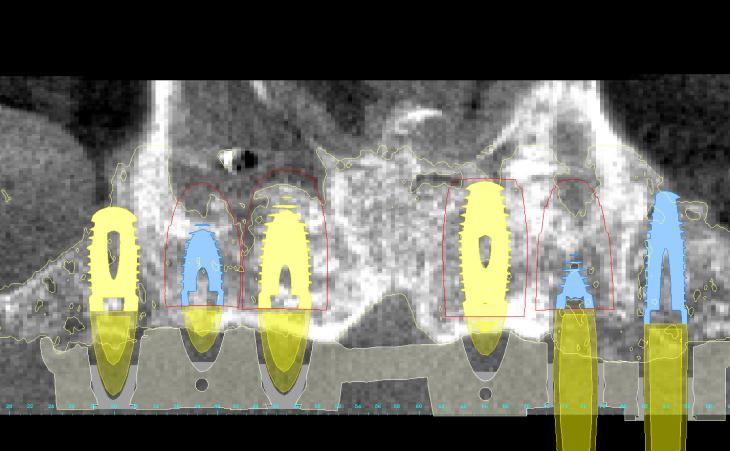

46 year old male has been missing his upper teeth for years and wore a denture. He had severe dental phobia . Using Advanced guided surgical technique, I was able to plan his entire surgery virtually, create a surgical guide (template) and place his implants in the most ideal positrons. Virtual planning held to shorted surgical time and thus improves technique and recovery.